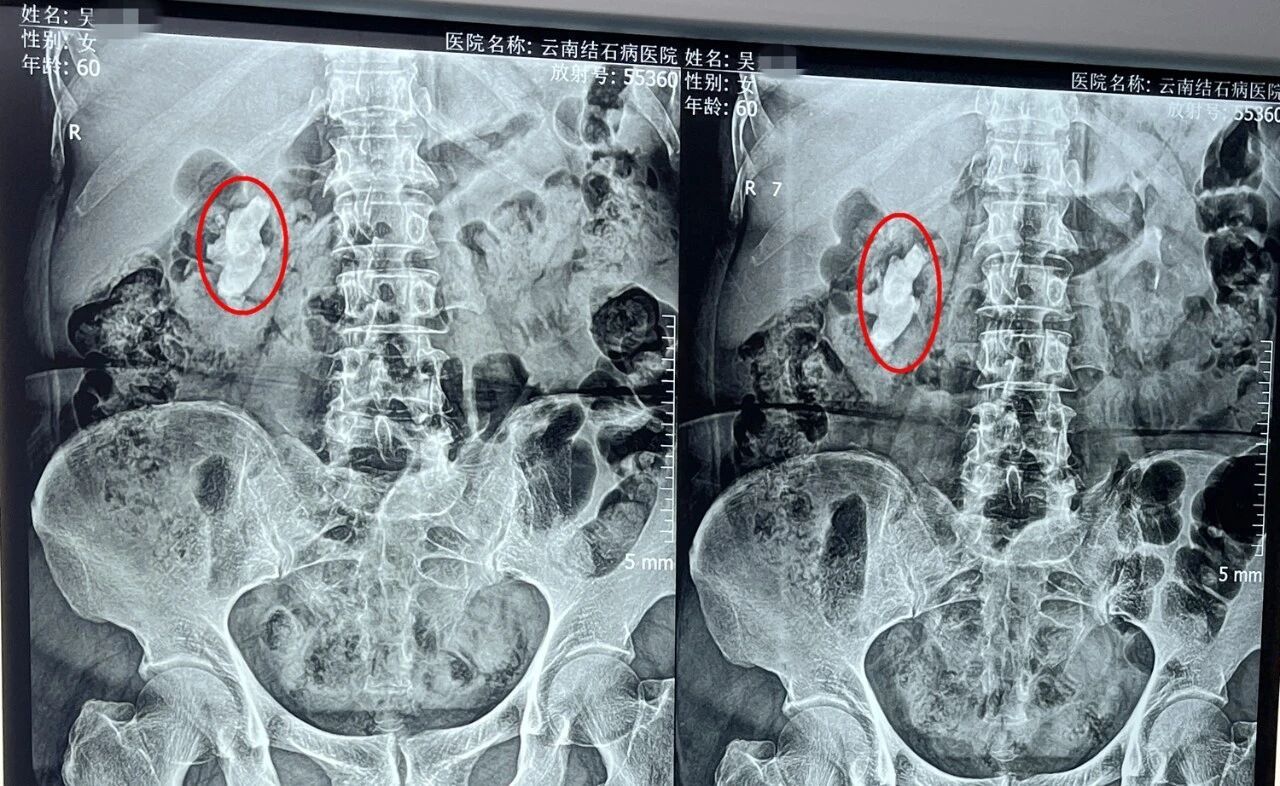

结石几乎遍布患者右肾

入院经过详细检查,泌尿外科黄鸿宾主任发现,吴女士的右肾上、中、下盏均遍布结石,其中最大一颗约3.6×2.7厘米,并且已经造成了右侧肾盂及部分肾盏的局限性积水。考虑到患者肾脏内结石大、硬度高(CT值达1098Hu),黄鸿宾主任为其制定了“经皮肾镜碎石取石术”的手术方案。

从患者右肾内击碎取出的结石